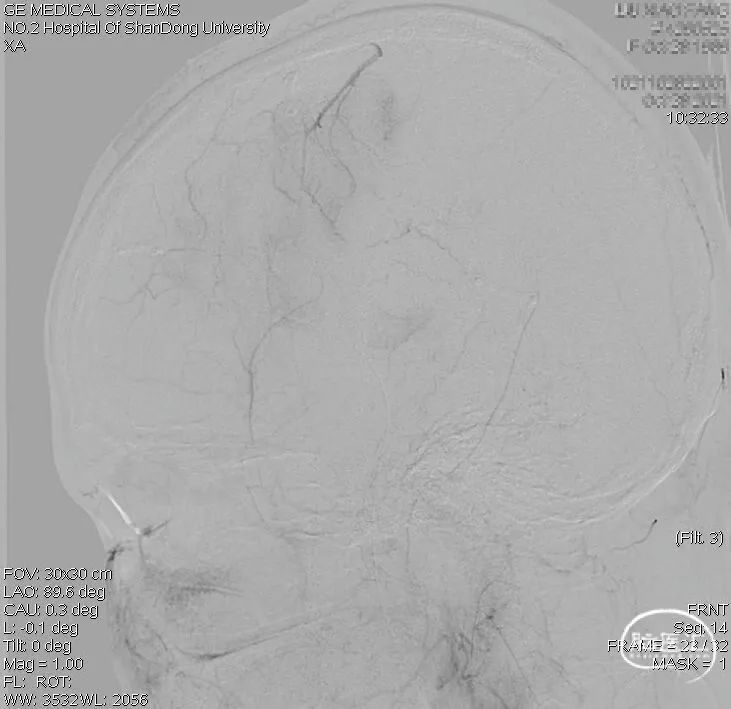

术前右颈内动脉正位: